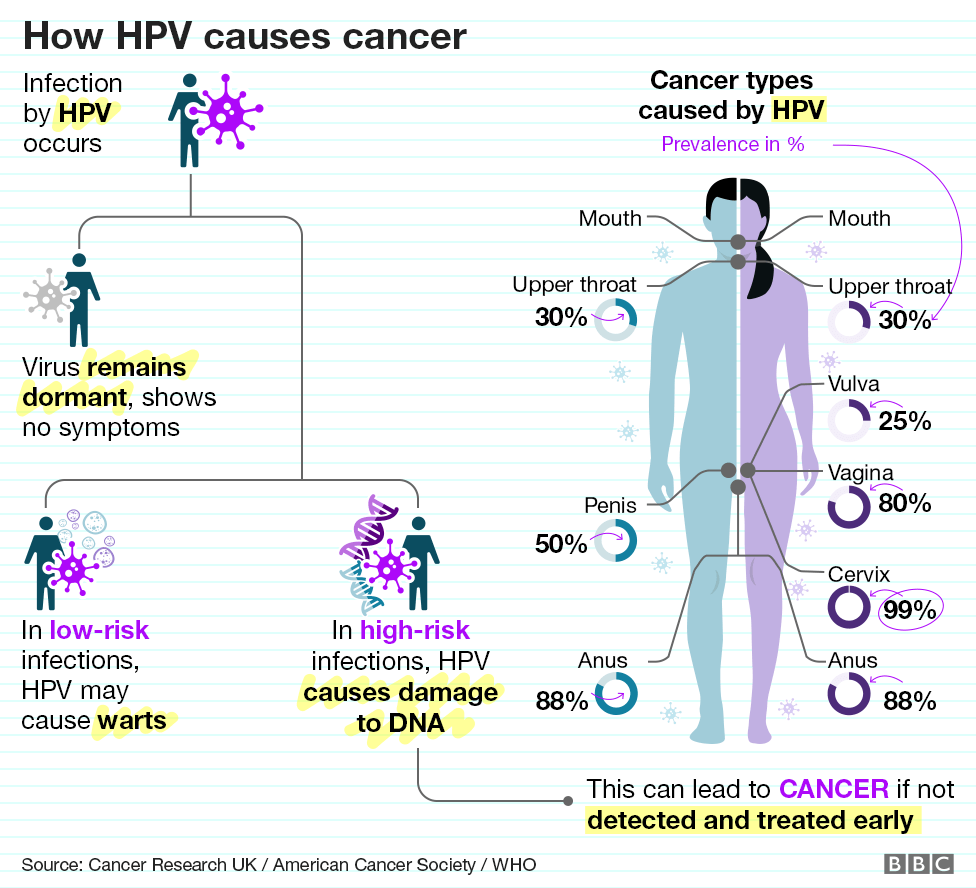

penile cancer photos download

Posts: penile cancer photos download